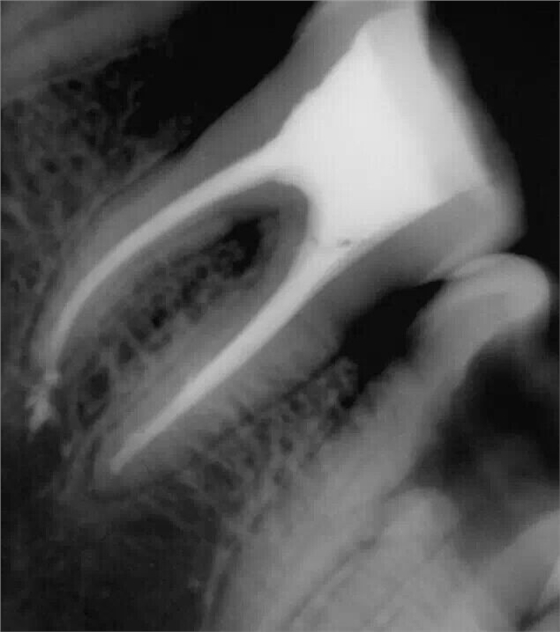

震出一半時照的X片